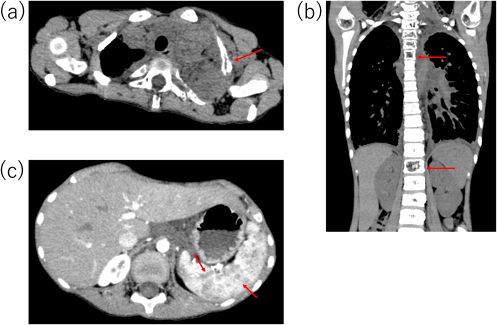

今後の治療方針を検討していたところ,心臓カテーテル検査後6カ月後頃から徐々に肋骨の突出が目立つようになり,圧痛も認めるようになった.造影CT検査を再検したところ,左第1・2肋骨の骨皮質欠損・骨溶解像(Fig. 4a)に加え,椎体の骨折(Fig. 4b),脾臓に多数の嚢胞状造影不良域(Fig. 4c)を認めた.特徴的な画像所見を有し,これまでの臨床経過と合わせてGLA/GSDの診断に至った.現在シロリムス内服治療を開始し約2年経過しているが,骨皮質は改善傾向で症状の増悪は認めていない.

GLA/GSDは,中枢神経系を除く骨や胸部(肺,縦隔,心臓),腹部(腹腔内,脾臓),皮膚,皮下組織など全身臓器にびまん性に異常に拡張したリンパ管組織が浸潤する,原因不明の希少性難治性疾患で,国内の推定患者数は約100人と言われている9).男女差や遺伝性はなく,小児,若年者に多いと考えられている.骨溶解を起こすGSDも,骨病変だけでなく同様の内臓病変を持つ場合があるため,類縁疾患と考えられ,現時点では一つの疾患としてとらえられている.症状は病変の浸潤部位により,胸部に生じた場合は胸水,乳び胸,心タンポナーデ,心不全など,また肺浸潤による息切れ,咳,喘鳴,呼吸苦,慢性呼吸不全を起こす.胸部単純X線写真やCT検査では,びまん性に広がる肥厚した間質陰影や胸水貯留,胸膜肥厚,心嚢水を認める.また骨に生じると,骨溶解,骨欠損による疼痛や病的骨折などを起こす.腹部に生じると,腹水や,脾臓内およびほかの腹腔内臓器に多発性の嚢胞性リンパ管腫病変を認める9).2018年に改訂されたThe International Society for the Study of Vascular Anomalies(ISSVA)分類では,脈管異常は内皮細胞の増殖性変化を有する脈管性腫瘍と,内皮細胞の増殖を認めず脈管の構造異常を主体とする脈管奇形に大別される.脈管奇形のうちの単純型にリンパ管奇形が含まれ,そのなかにGLA/GSDは含まれる10).診断基準をTable 2に示す.(1)のa)~c)のうち一つ以上の主要所見を満たし,(2)の病理所見を認めた場合に診断する.病理検査が困難な症例は,a)~c)のうち一つ以上の主要所見を満たし,臨床的に除外疾患を否定できる場合に限り,診断可能とされている.本症例は病理検査を行っていないが,骨溶解,心タンポナーデの既往,脾臓のリンパ管腫症様病変と主要所見のa)~c)を全て満たし,これまでの経過からリンパ管造影などのさらなる画像検査は行っていないが,GLA/GSDと診断した.

収縮性心膜炎は,心膜の肥厚が原因とされ,成人では4 mm以上の壁厚が肥厚と判定される13).心臓超音波検査における拡張障害や,心臓カテーテル検査における心内圧曲線でdip and plateauが特徴的とされる.dip and plateau波形は,ゼロ以下の拡張期下降から急峻な立ち上がりで拡張期plateauに続き,拡張期plateau圧は収縮期の3分の1を超えるとされている14).本症例は心膜肥厚を疑う所見を認め(Fig. 2),心臓超音波検査で拡張障害は明らかでなかったが,その時点ではGLA/GSD病は鑑別に挙がっておらず,病歴からも収縮性心膜炎の可能性が高いと考えられたため,心臓カテーテル検査を行った.しかし,心臓カテーテル検査でもdip and plateau型の心内圧曲線は認めず(Fig. 3),収縮性心膜炎は否定的であり,心筋生検も行ったが心筋症も否定された.

その後骨病変を機にGLA/GSDの診断に至った.厚生労働省難治性疾患克服研究事業のリンパ管腫症研究班が定めた「リンパ管腫症・ゴーハム病の診断基準」では,Table 2に示したように,主要臓器である骨,胸部,腹部のなかの一つ以上の臓器にリンパ管組織やリンパ液が貯留すること,および病理学的検査で鑑別すべき疾患を否定し,拡張したリンパ管内皮細胞を証明することによって診断可能であるが,病理検査がない場合でもほかの疾患を否定できれば臨床的に診断可能となっている15).また,診断基準となる必須項目の画像診断は胸部CTの特徴的所見とされており,本症例ではリンパ管造影を施行しなかった.本症例は心タンポナーデ発症から診断までに6年を要した.その間様々な検査を行ったが肺間質陰影増強の原因特定に至らず,今回病理検査は行っていないが収縮性心膜炎など他疾患も否定できたため,特徴的な画像所見と合わせ臨床的にGLA/GSDと診断した.